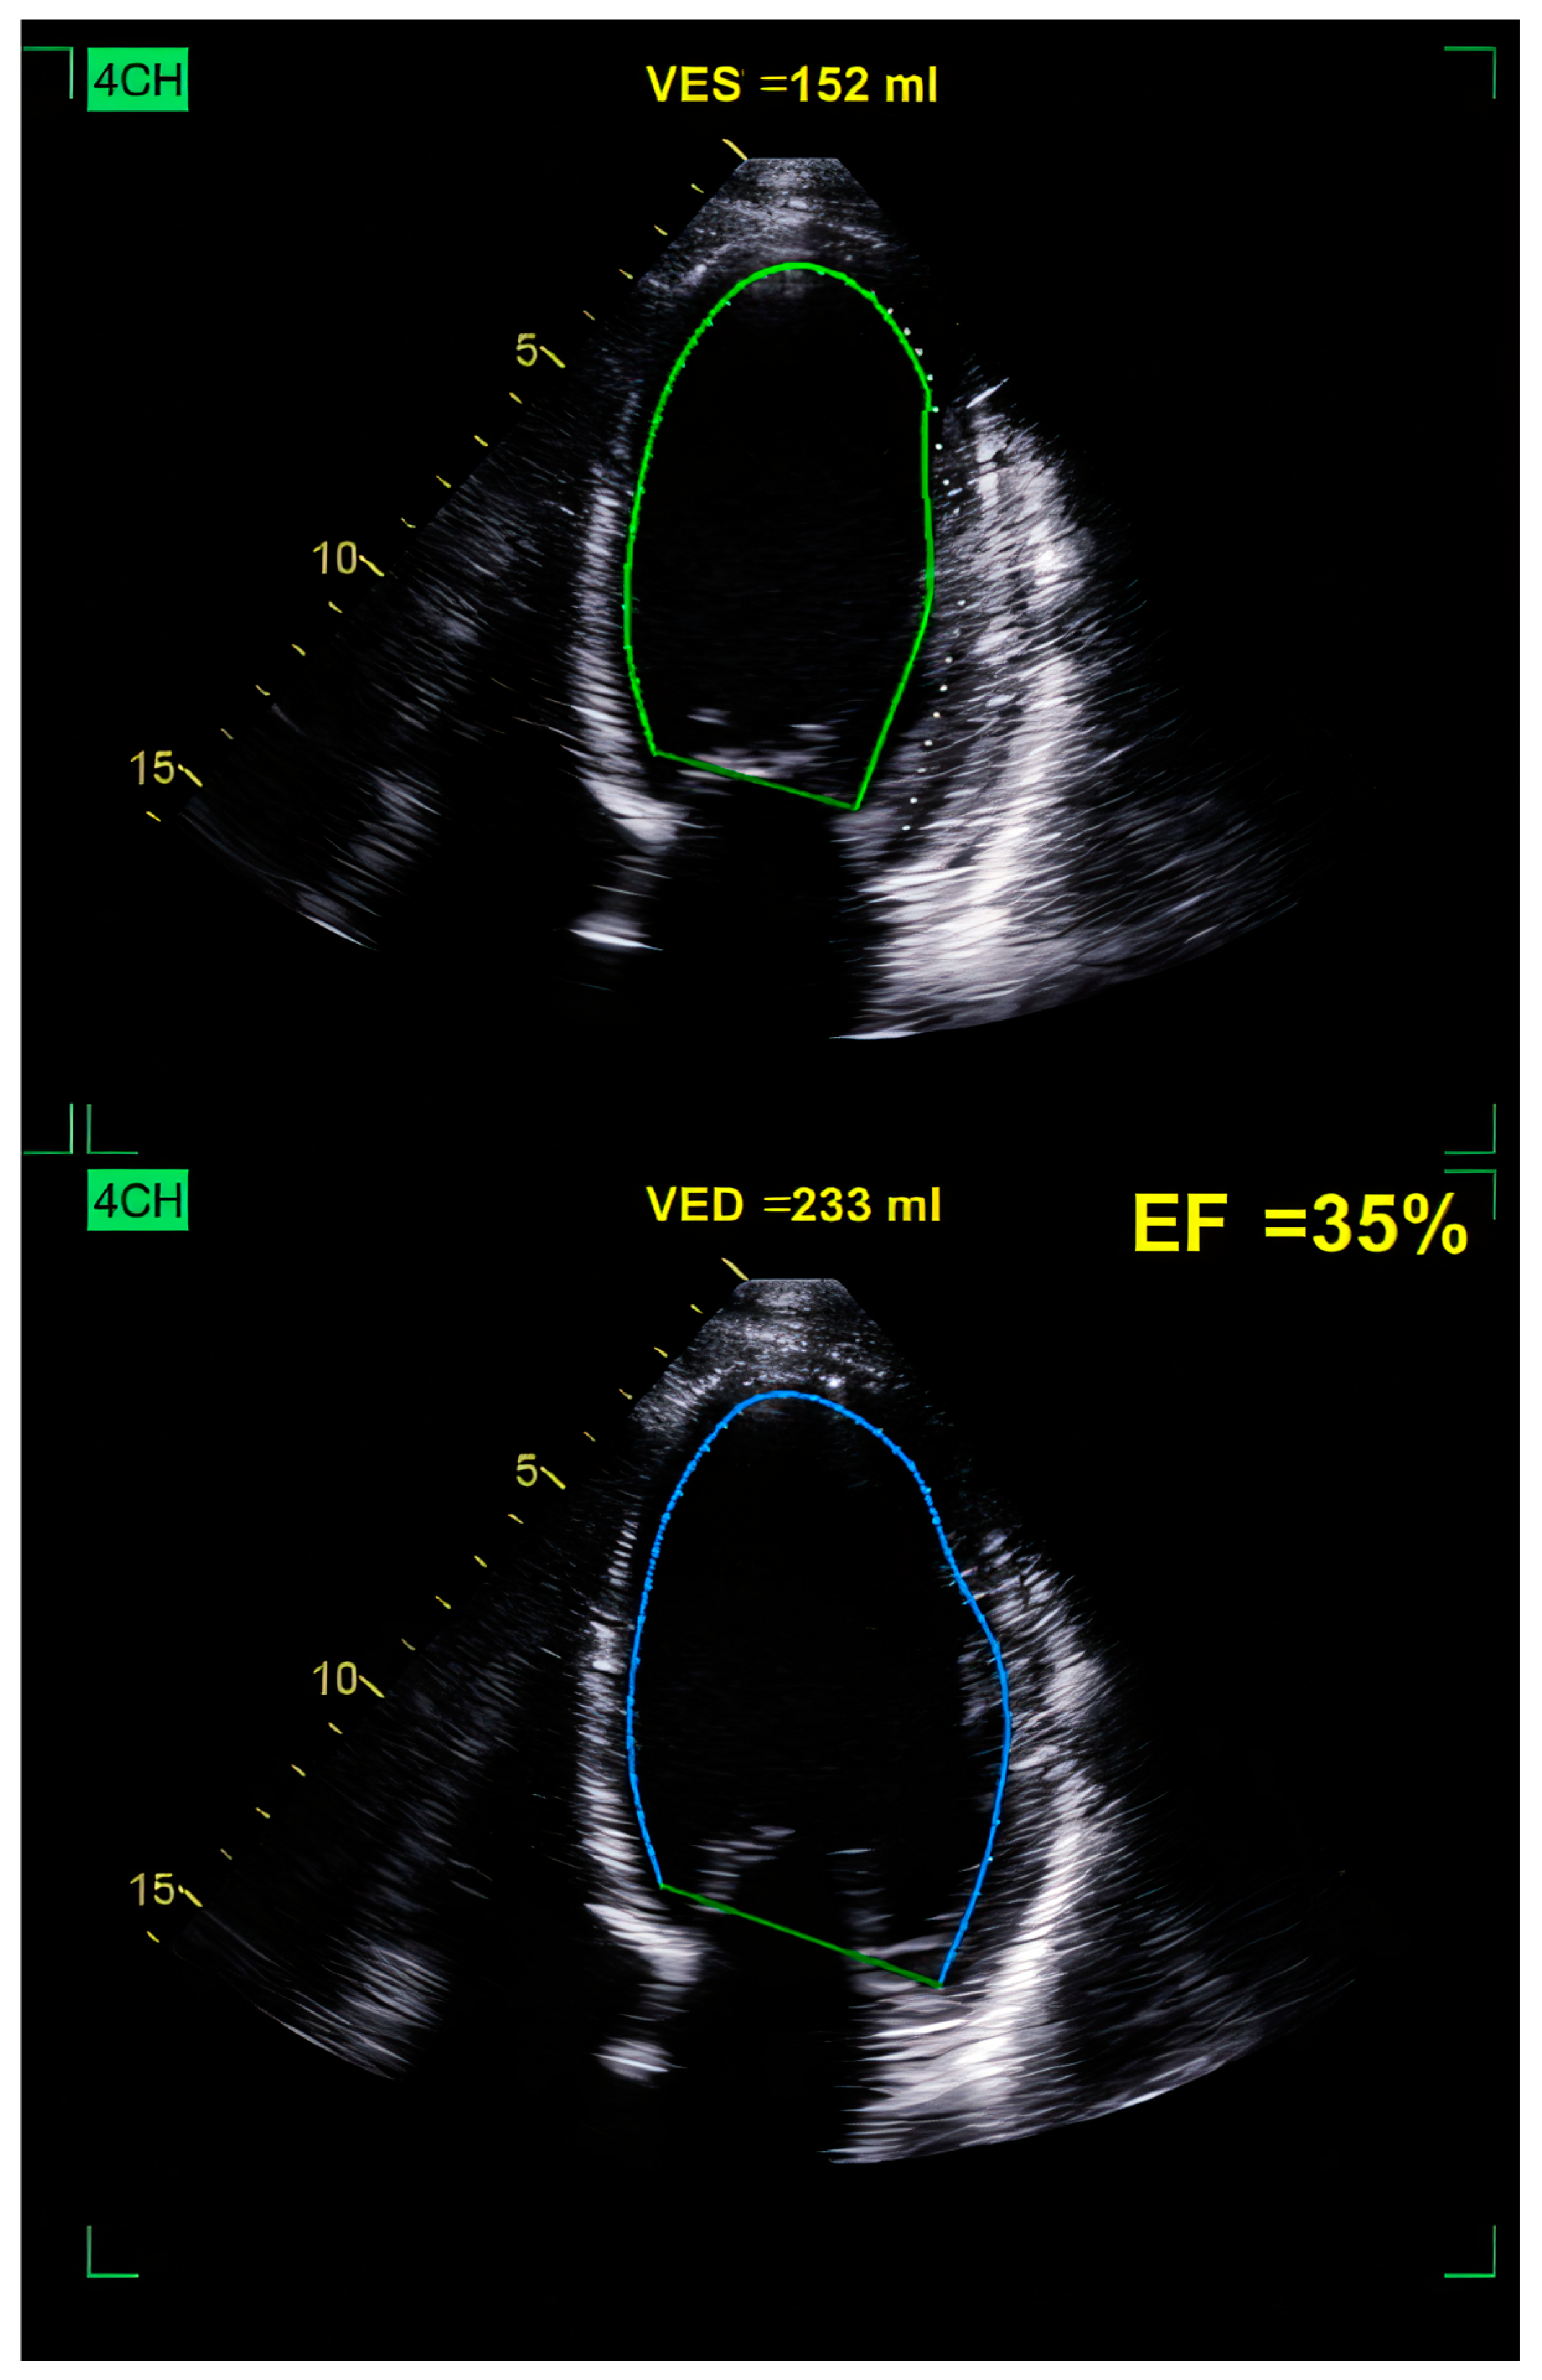

10.3.1. Echocardiography